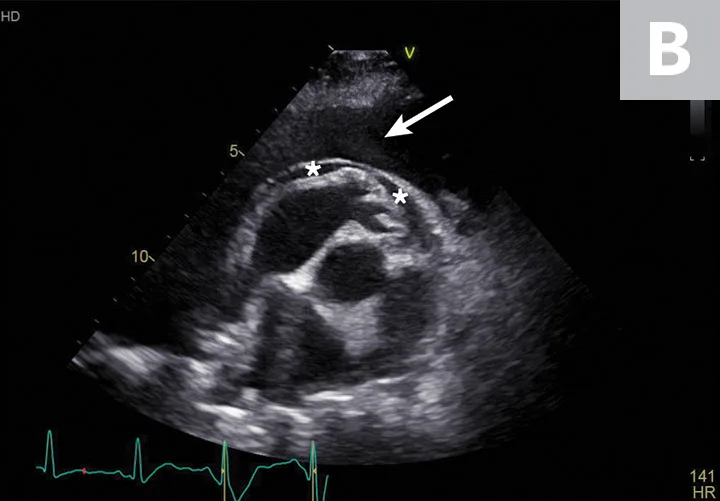

FIGURE 2

Abdominal effusion (A; asterisk) adjacent to a normal spleen (arrow). Abdominal carcinomatosis with secondary neoplastic effusion was diagnosed. Left parasternal short-axis view of a heart with pericardial (B; asterisks) and pleural effusion (arrow).